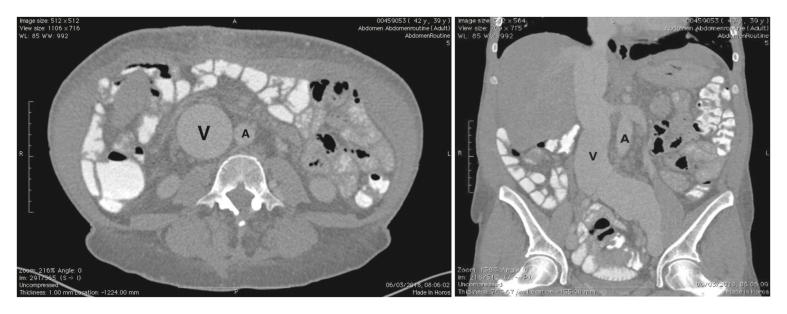

A 40 year old man with past history of gunshot wound of the right flank complained of severe right limb swelling and shortness of breath. An AVF between the right external iliac artery and external iliac vein responsible for the cardiac failure was diagnosed. A 40 year old woman with past history of spinal surgery complained of breathlessness and lower limb oedema. She presented with recurrent episodes of ascites and dyspnoea. An AVF between the right common iliac artery and the common iliac vein responsible for high output cardiac failure was diagnosed. Open surgery was performed in both patients and treatment of the AVFs led to the resolution of all symptoms. Follow up at four and three years, respectively, was uneventful in both cases.

一名40岁男性,既往有右侧腰部枪伤史,主诉右下肢严重肿胀和呼吸急促。诊断为右髂外动脉与髂外静脉之间的AVF导致心力衰竭。一名40岁女性,既往有脊柱手术史,主诉呼吸急促和下肢水肿。她反复出现腹水和呼吸困难。诊断为右髂总动脉与髂总静脉之间的AVF导致高输出量心力衰竭。两名患者均接受了开放手术,AVF的治疗使所有症状得到缓解。分别在术后四年和三年进行随访,两例均无异常。